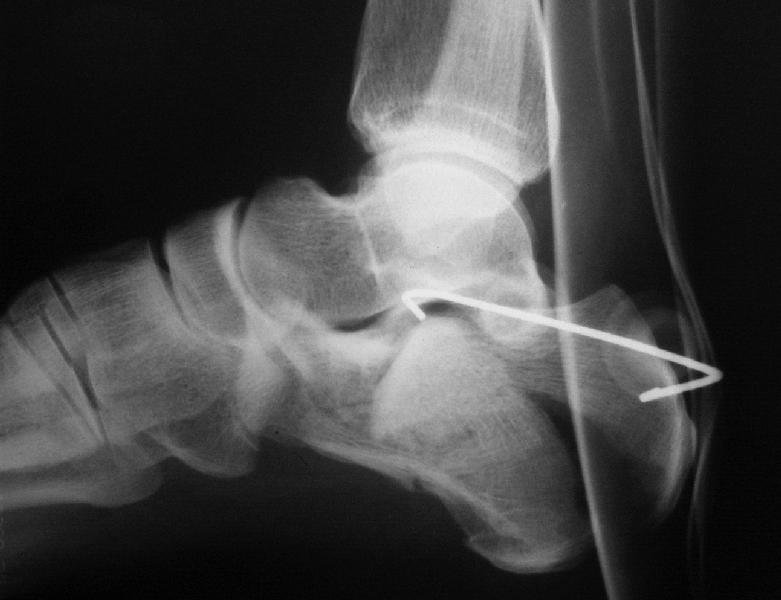

Окончательная фиксация спицами, пяточными пластинами (5) , в последнее время стали применять крючковидные пластины (ДЕОСТ) (6,6a).

Кроме стандартных снимков, необходим контроль конгруэнтности суставной поверхности (проекции Бродена)